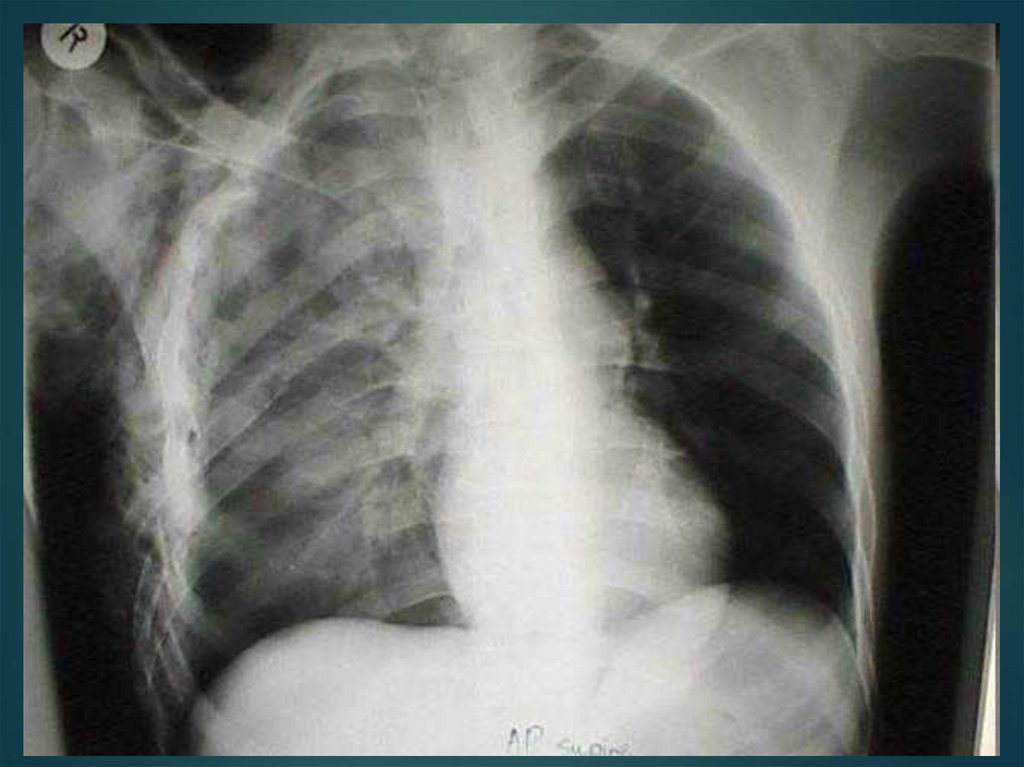

48. Закрытый пневмоторакс

возникает в результате быстрого

Состояние средней тяжести, бледность кожных

покровов, одышка. При аускультации ослабление

дыхания на стороне поражения. При перкуссии –

коробочный звук в верхних отделах грудной клетки

49. Закрытый пневмоторакс

Небольшое количество воздуха (300—500 см3)

рассасывается в течение 2—3 нед. Если легкое

поджато более чем на 1/4 своего объема,

производят плевральную пункцию для

максимального удаления воздуха.